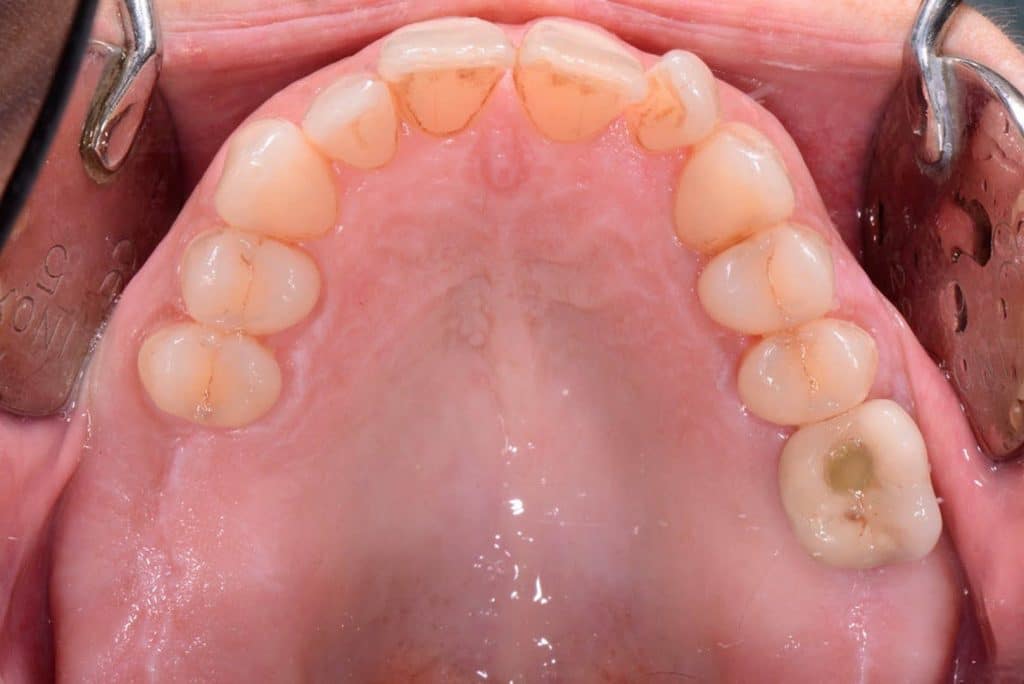

The crest is cut with a size 15 Bard-Parker scalpel, and a full-thickness flap is made performing a double widening suture both buccally and palatally. The first bur to be used is the Locator Drill that works only for 3.5 mm and only drills the cortical bone.Subsequently, I used the 1.2 mm diameter Probe Drill.